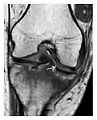

High-energy trauma fractures

Figure 3: A 26-year-old man presenting with wrist pain after being assaulted. (a) Initial anteroposterior radiograph shows a subtle linear lucency within the scaphoid extending to the scaphocapitate articular surface that was overlooked (arrow). (b) Initial "scaphoid" view was negative. (c) Followup anteroposterior radiographs, 12 days later, shows obvious scaphoid fracture (arrows).[1]